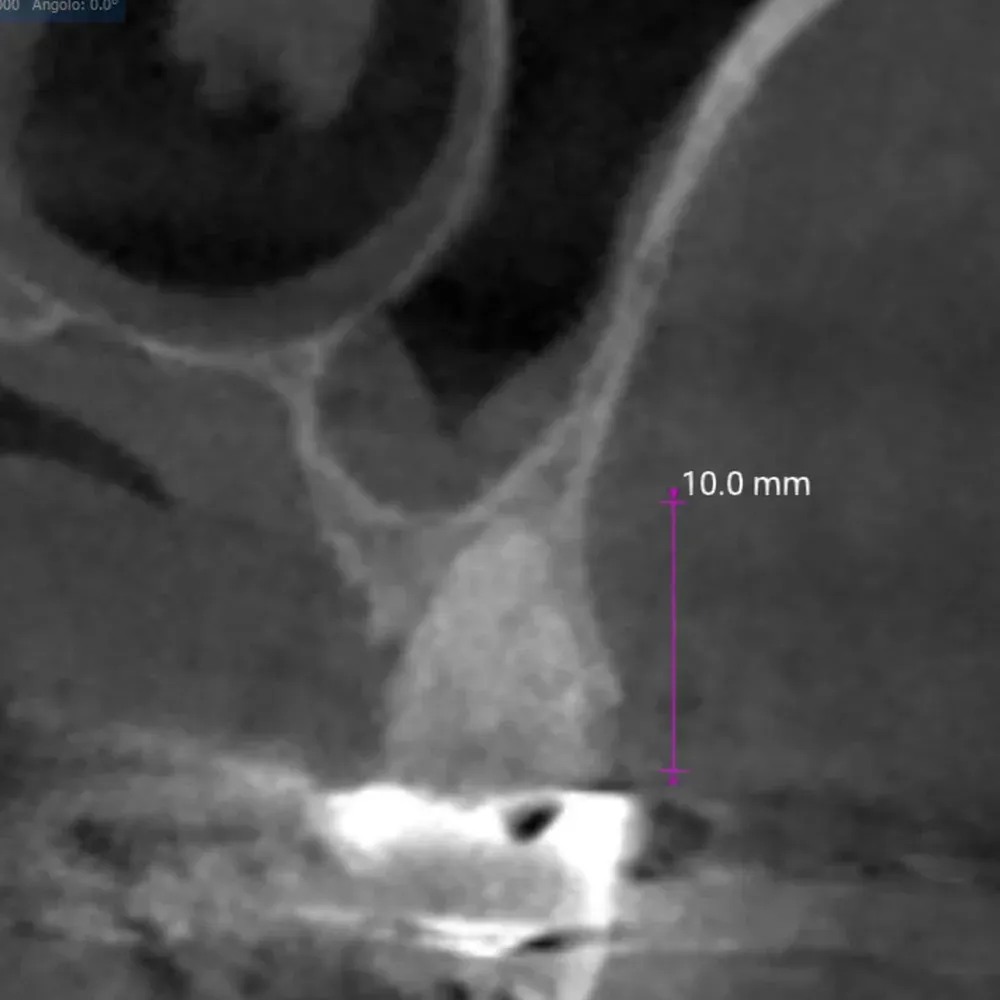

La CBCT dimostra l’anatomia atrofica della zona, con la vicinanza del pavimento del seno mascellare e la significativa perdita di sostanza palatale dovuta all’infezione parodontale.

CBCT di elemento dentario 2.5 affetto da carie e tasca parodontale acuta

CBCT dell’elemento 2.5 con evidenza della vicinanza del seno mascellare e della distruzione del parodonto, soprattutto sul versante palatino.

CBCT Post-op: Impianto in posizione 2.4 infracrestale che ha raggiunto la posizione di ingaggio corticale corretta

Espansore in posizione 2.5 con sollevamento della corticale del pavimento del seno

CBCT Post-op: Impianto in posizione 2.5 infracrestale con sollevamento della corticale del pavimento del seno

L’aumento della densità ossea intorno all’apice dell’impianto in posizione 2.5 è evidente, particolarmente in zona mesiale. In quella zona, la corticale del seno si è sollevata maggiormente.